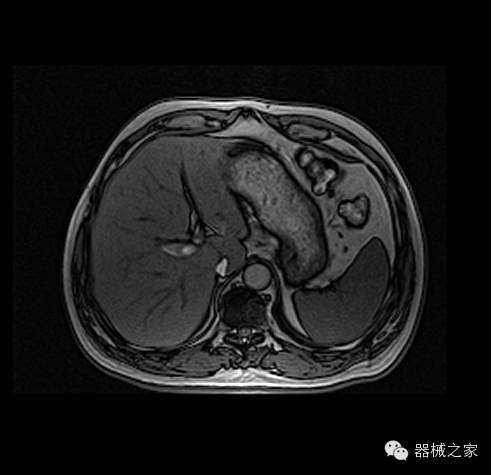

临床图片赏析

头部T2加权像

腹部反相位像

头部MRA成像